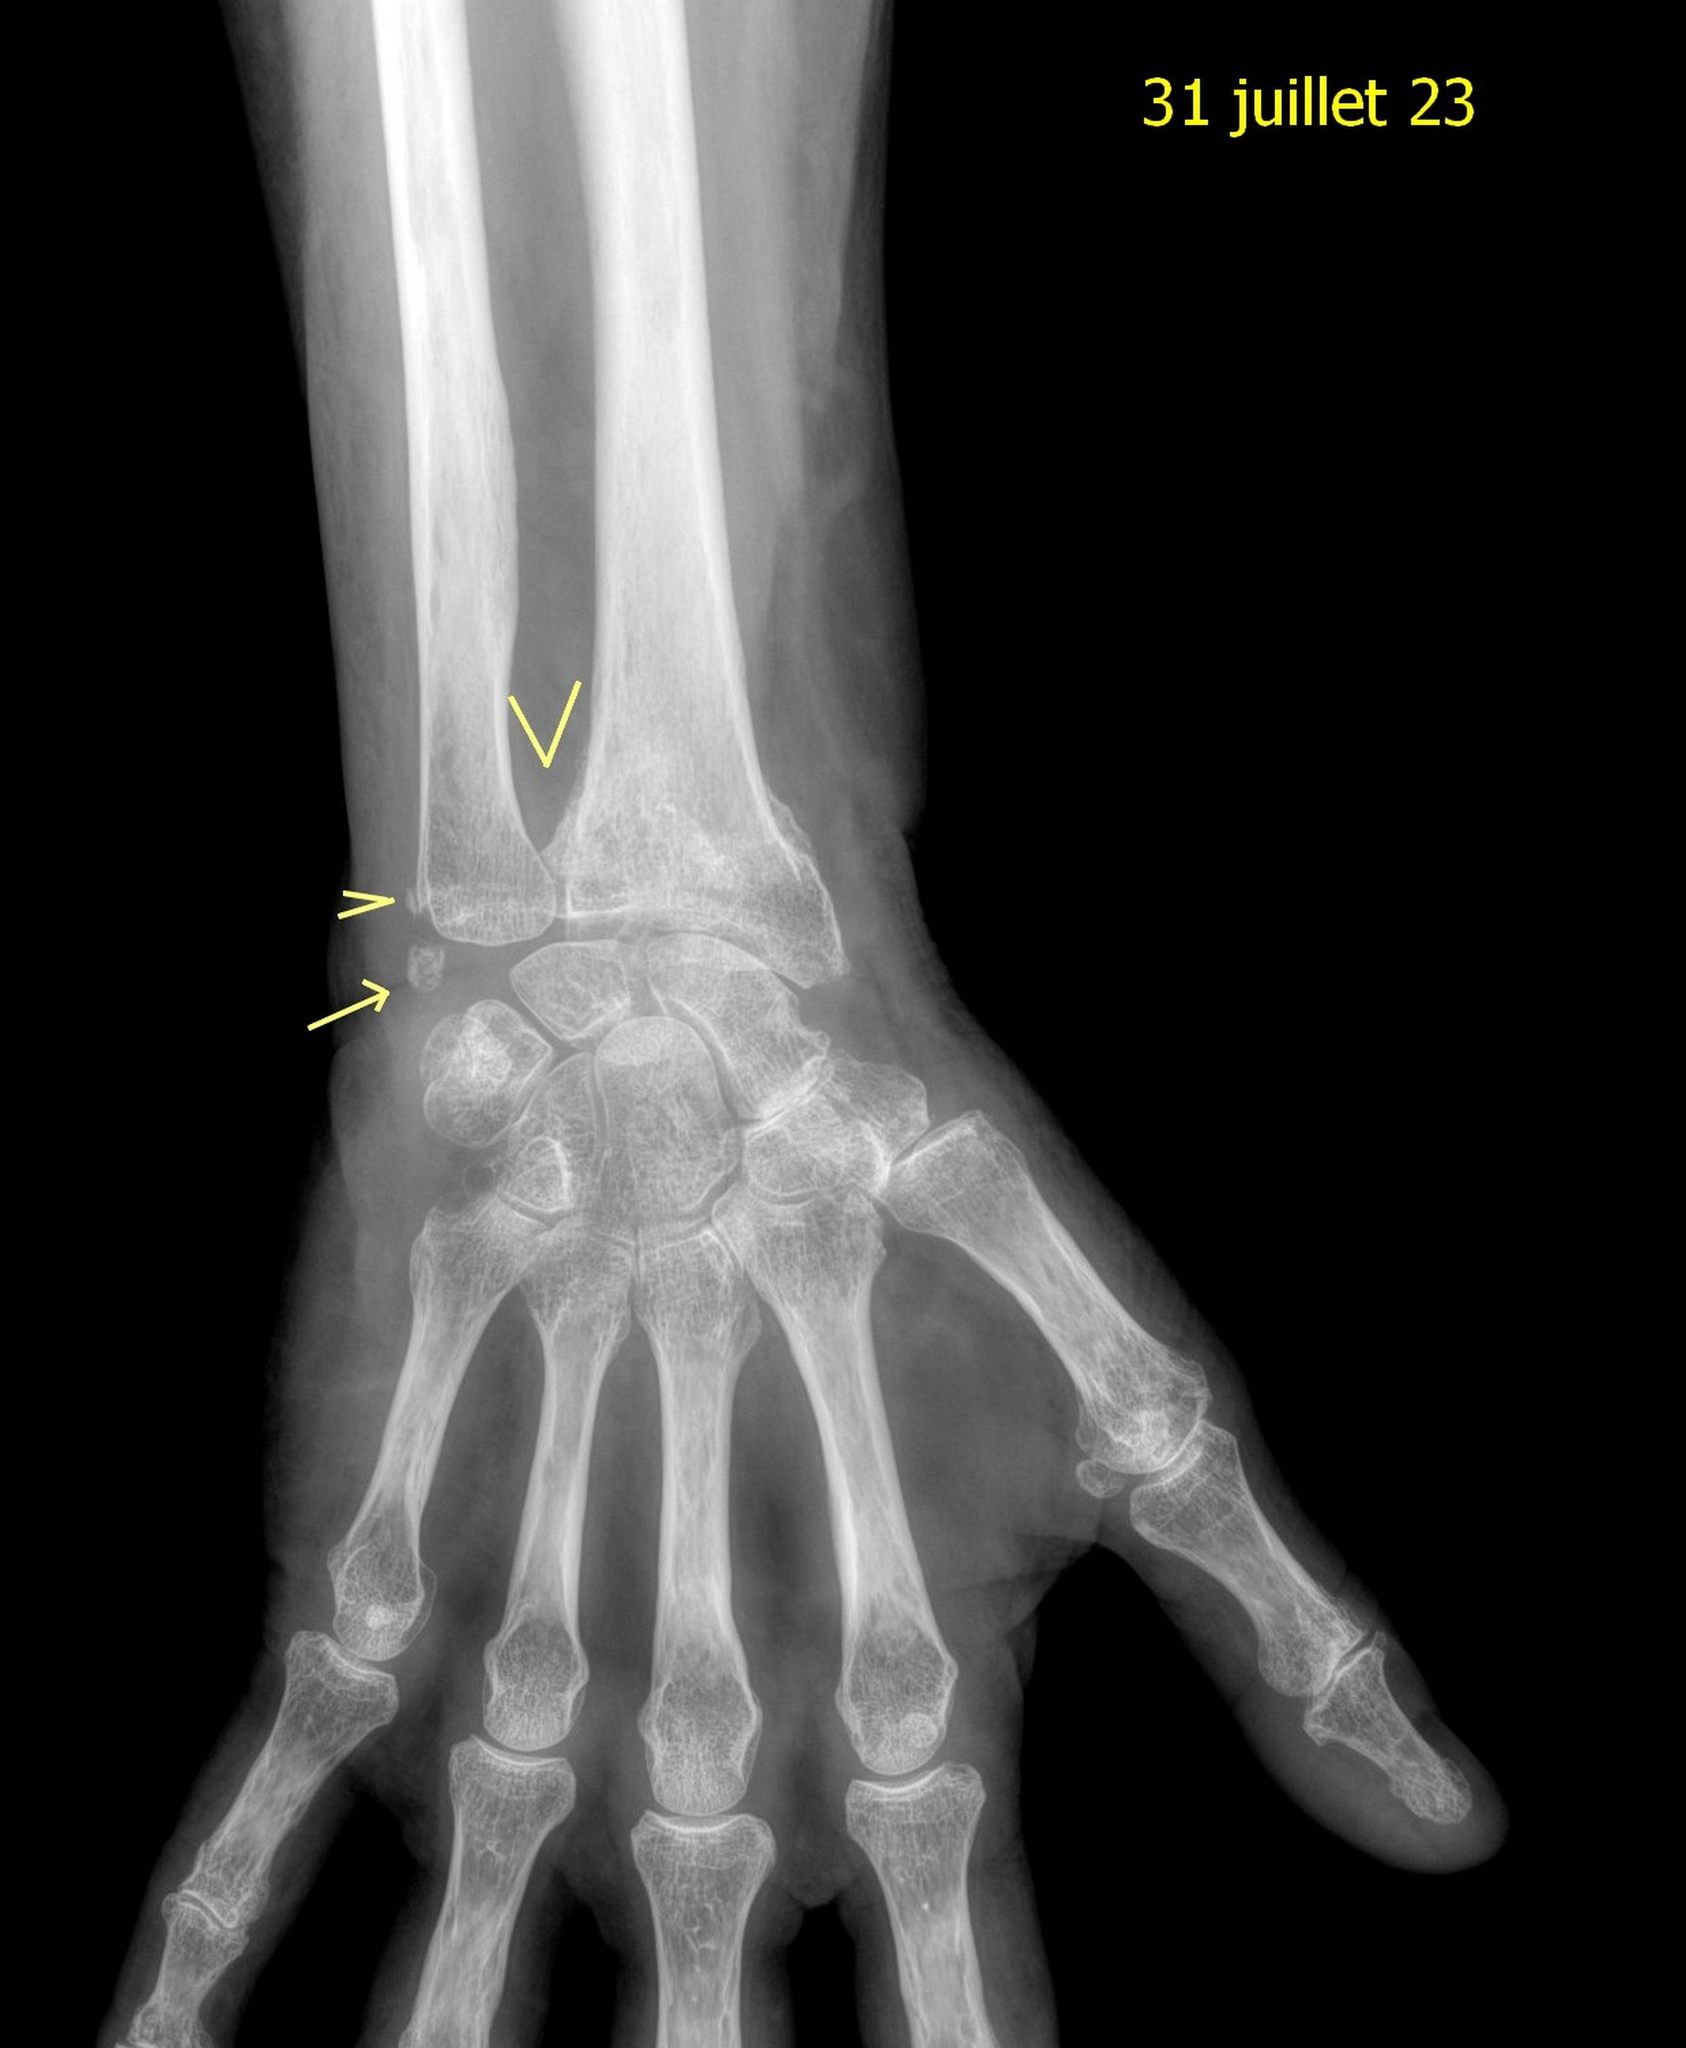

Alors oui la consolidation a commencé mais elle a attaché le radius et le cubitus , voilà pourquoi je ne sais plus tourner l’avant bras. Forcément mes mouvements s’en trouvent limités et ça restera comme ça.